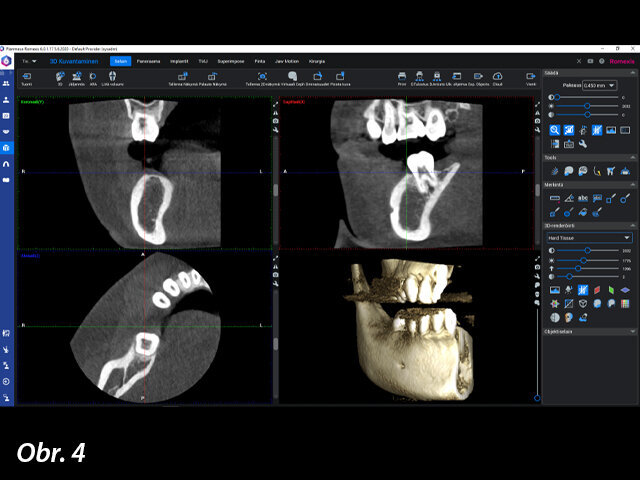

Pro naplánování implantologického ošetření byl nejprve pořízen CBCT snímek pomocí rentgenu Planmeca Viso G7 a zuby byly oskenovány intraorálním skenerem Planmeca Emerald. CBCT snímek a intraorální sken byly zkombinovány v softwaru Planmeca Romexis. Plánování ošetření bylo provedeno v modulu Planmeca Romexis 3D Implant, který obsahuje knihovnu implantátů od více než 100 výrobců. Pro pacientku byl zvolen implantát CONELOG SCREW-LINE od společnosti CAMLOG s průměrem 4,3 mm a délkou 9,0 mm, a jeho zavedení pak bylo pečlivě naplánováno pomocí režimu náhledů na implantát, který je součástí výše uvedeného softwaru.

Plánování implantátu bylo provedeno v softwaru Planmeca Romexis.